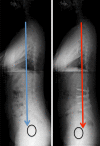

Material and method: The authors proposed their method for the osteotomy planning paying attention to the pelvic, and spine parameters and in accordance with Roussouly's classification. The pre operative planning is based on a full-body X-ray including the spine from C1 to the femoral head and the first 10 cm of the femur shaft. Using all the balance parameters provided, a formula name FBI is proposed. Calculation of the osteotomy is basic goniometry, the midpoint of the C7 inferior plateau (point a) is transposed horizontally on the projected future C7 plumb line (point b) crossing posterior S1 plateau on a sagittal X-ray. These are the first two reference points. A third reference point is made on the anterior wall of the selected vertebra for osteotomy at mid height of the pedicle (point c) mainly L4 vertebra. These three points form a triangle with the tip being the third reference point. The angle represented by this triangle is the theoretical angle of the osteotomy. Two more angles should be measured and eventually added. The femur angulation measured as the inclination of the femoral axis to the vertical. And a third angle named the compensatory pelvic tilt to integrate the type of pelvis. If the pelvic tilt is between 15 and 25° or is higher than 25° you must add 5 or 10°, respectively. This compensatory tilt is based on a clinical analysis of operated patients.